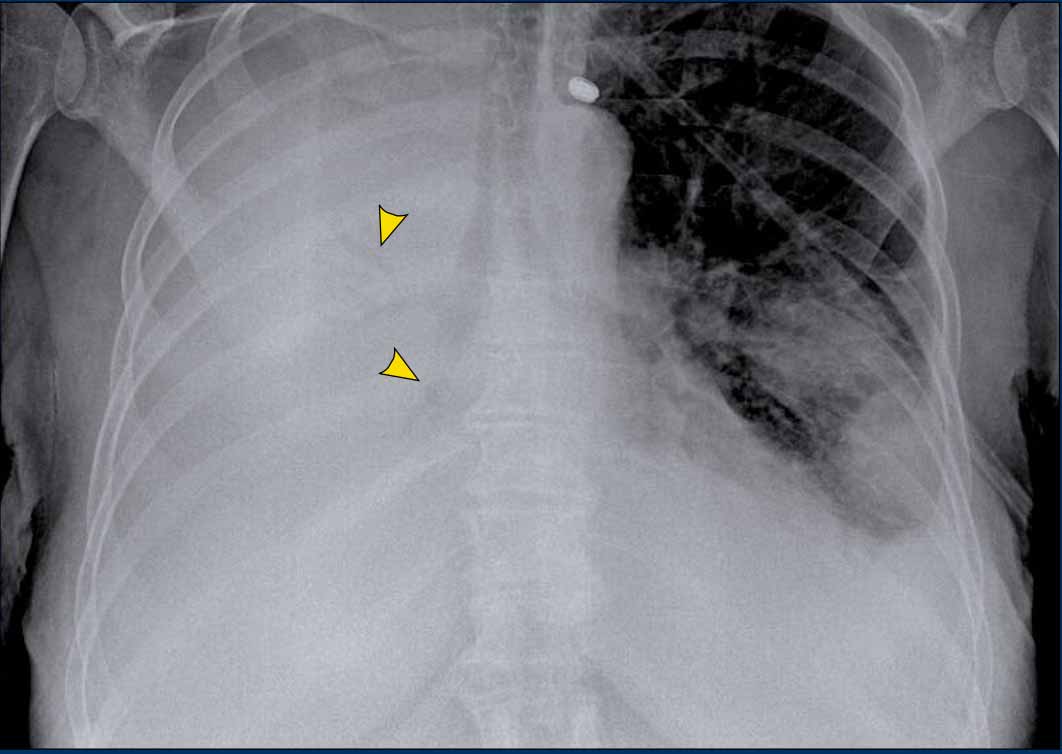

• Case Example

A patient with bilateral carcinomatous pleuritis.

Findings

• Complete opacification of the right hemithorax.

• Air bronchogram in the right main bronchi (arrowheads), indicating compression atelectasis of the lung due to massive effusion.